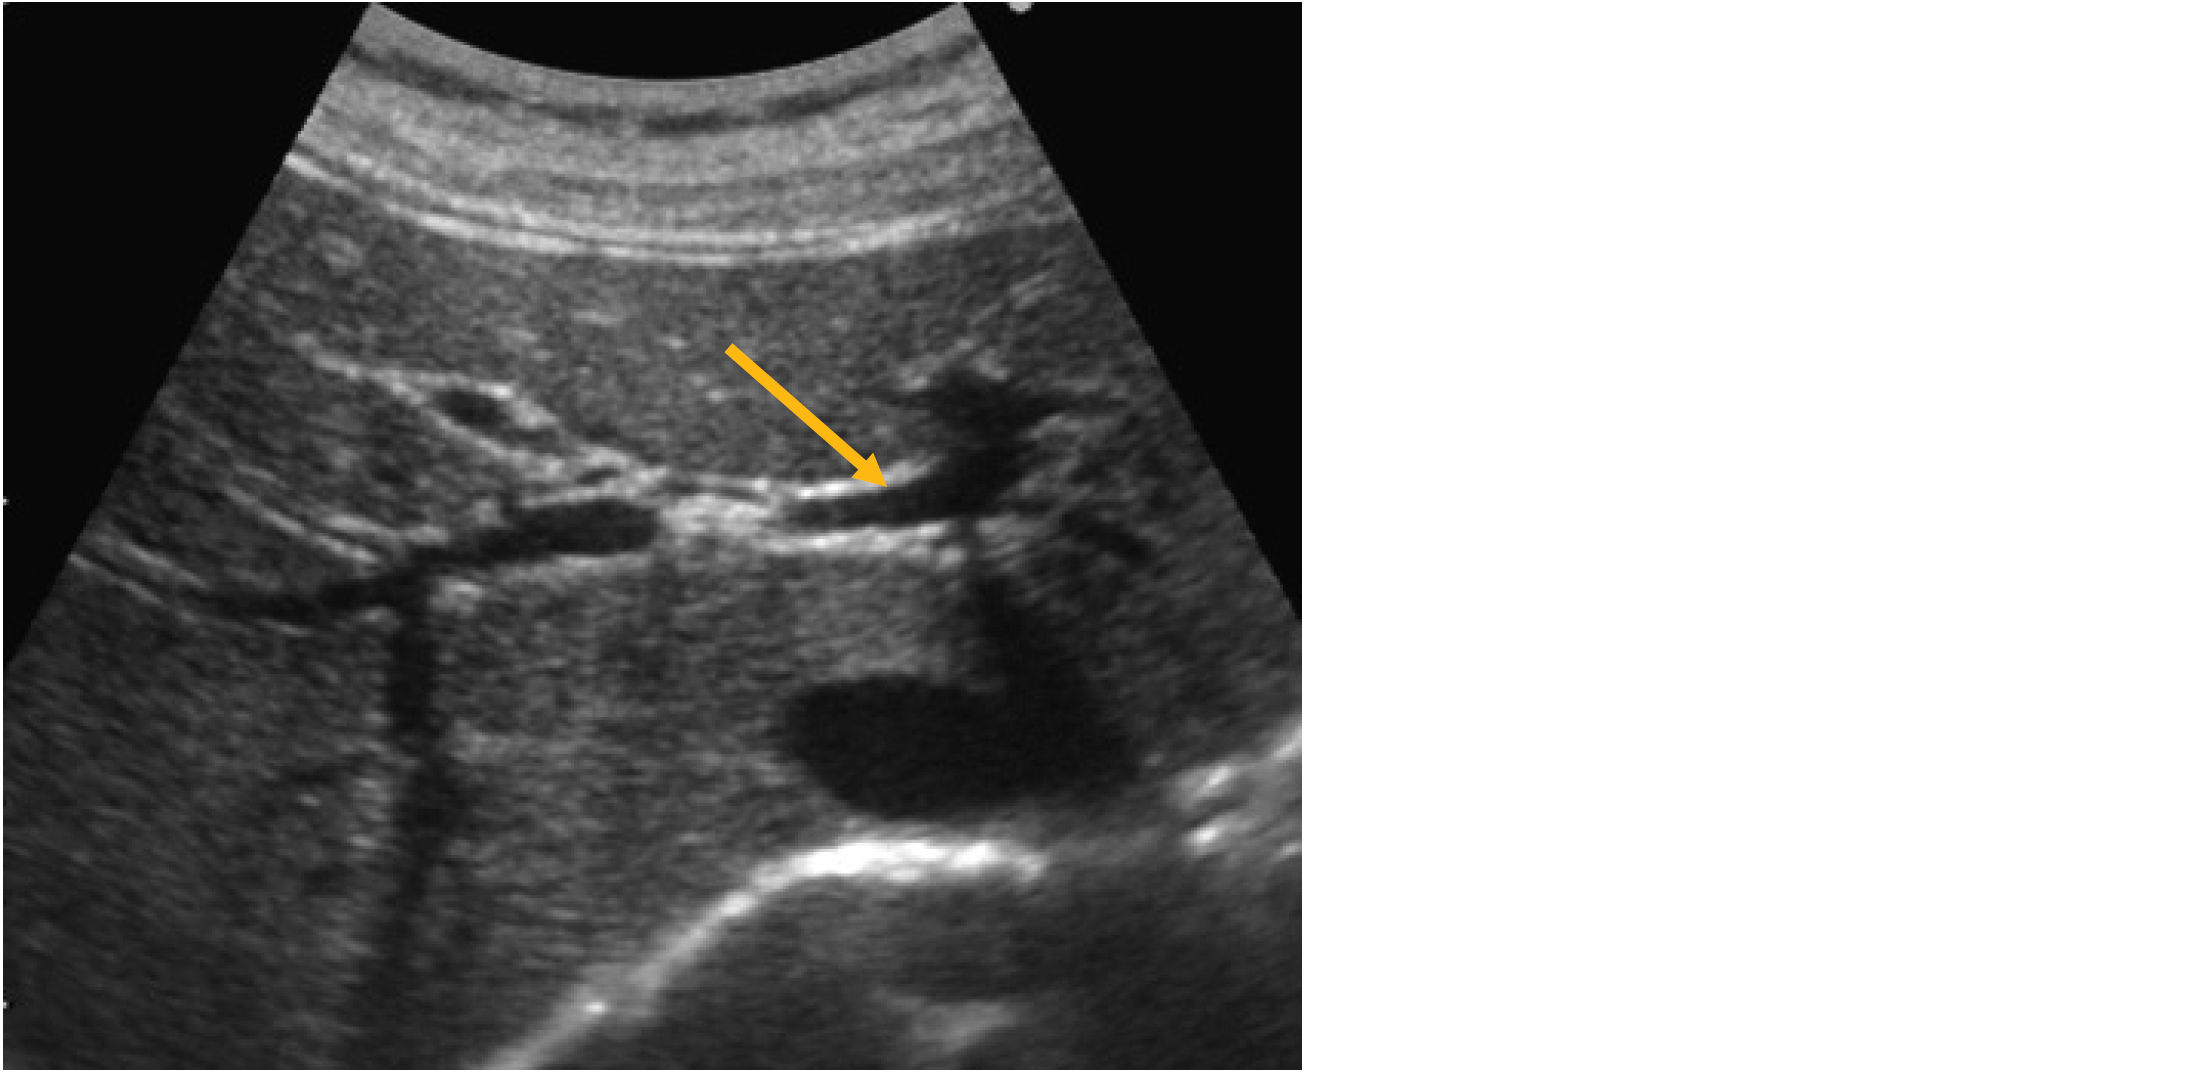

心窩部斜走査による上腹部の超音波像を示す。

矢印で示すのはどれか。

1. 左肝静脈

2. 中肝静脈

3. 右肝静脈

4. 門脈左枝

5. 門脈右枝